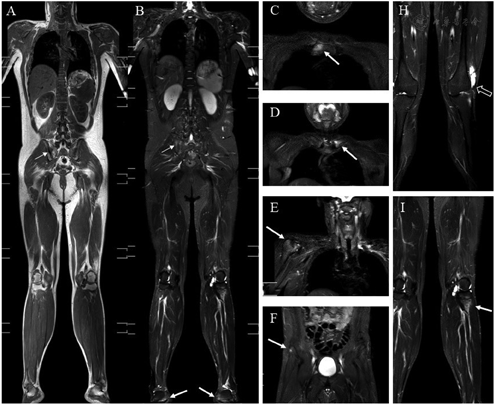

The number and frequency of enthesitis evaluated by WB-MRI and clinically for the individual entheses are shown in [Supplementary Figure 1, http://links.lww.com/CM9/A794]. A total of 450 entheseal sites were evaluated clinically. Clinical enthesitis was observed in 54 of 450 (12%) entheseal sites. The largest proportion of inflammation was detected in the anterior chest wall (n = 24, 44%). The mean clinical enthesitis score was 1.9 ± 2.4 out of 15 possible scoring points. WB-MRI identified enthesitis in 97 of 1020 (9%) entheseal sites. The maximum number of enthesitis cases was detected in the pelvis (27, 28%): including iliac crest one, anterior superior iliac spine three, posterior superior iliac spine 0, ischial tuberosity ten, pubic symphysis four, greater femoral trochanter nine, and lesser femoral trochanter 0. The foot had the least number of enthesitis (12, 12%) cases, whereas the Achilles tendon had eight enthesitis cases. Imaging examples are presented in [Figure 1].

WB-MRI was performed on a Philips 3T Ingenia unit (Philips Healthcare, Best, Netherlands) using phased-array coils with patients in supine position. The technical MRI parameters are shown in [Supplementary Table 1, http://links.lww.com/CM9/A794]. The following 18 locations were evaluated and subdivided into five regions: region 1 included shoulder—acromioclavicular joint and supra-spinatus tendon; region 2 included anterior chest wall— costosternal joints, sternal synchondrosis, and sternoclavicular joints (SClJs); region 3 included pelvis—iliac crest, anterior superior iliac spin, posterior superior iliac spin, ischial tuberosity, pubic symphysis, greater femoral trochanter, and lesser femoral trochanter; region 4 included knee—medial femoral condyles, lateral femoral condyles, condyles lateralis tibiae, and caput fibulae; and region 5 included foot—proximal insertion of the Achilles tendon and plantar aponeurosis. Thirty-six points were assessed for each patient, and a total of 1080 points were assessed for all participants. All MR images were scored independently by two musculoskeletal radiologists. Enthesitis was diagnosed when a high signal intensity on short TI inversion recovery (STIR) images was obtained with a corresponding signal loss on T1-weighted images within the bone marrow (bone marrow edema [BME]) or the surrounding soft tissue (soft tissue edema). WB-MRI was scored dichotomously.